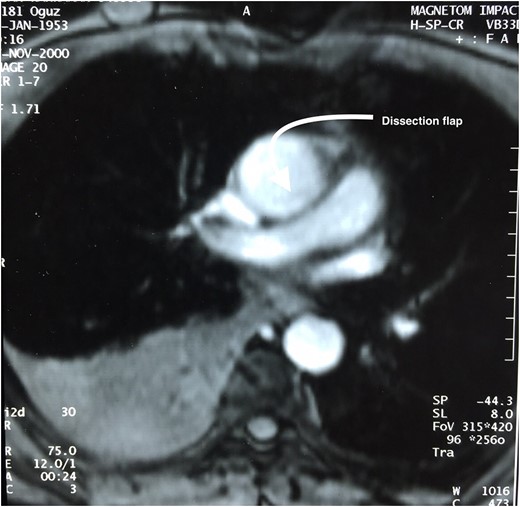

Meanwhile, TEE revealed myxomatous mitral and aortic valve, severe aortic valve insufficiency, moderate to severe mitral valve insufficiency, mild tricuspid valve insufficiency, ascending aorta and sinus valsalva dilation of 46 mm. A contrast computed tomography (CT) scan was performed and revealed ascending aorta dilatation of 48.5 mm without aortic dissection and sinus valsalva of 46 mm (Fig. 1). The descending aorta appeared to be normal, measuring 26.5 mm at its widest diameter.

Thorax CT angiography showing the dilatation of ascending aorta of a patient before surgery on admission to our center.

After observing such unexpected case (resembling type II aortic dissection) on surgery a patient was then questioned for further details on his medical history. Fifteen years ago, he was presented emergently to a cardiologist with chest pain, palpitation and sweating. On physical examination, he was hypotensive with sinus tachycardia. Both echocardiography and thorax magnetic resonance (MR) revealed pericardial effusion on posterior side of the heart (hemopericardium) with dissection flap (Fig. 3). His follow-up period was uneventful and he was then discharged from hospital with medical therapy, Echocardiography control (every 6 months) and thorax CT control (every 1 year). The last thorax CT (that we took in our clinic did not demostrate dissection flap (Fig. 1). Both imagings of Figs 1 and 3 were avaluated under the same radyologic level for accuracy.

Transthoracic two-dimensional echocardiography (TTE) is very effective in evaluating the aortic root, but the mid and distal ascending aorta, aortic arch and descending aorta are not seen. It also provides important information on aortic valvular regurgitation, and the function and dimensions of the left ventricle (4). Our patient was diagnosed with TTE that revealed only the dilatation of aorta without dissection. For further evaluation contast thorax CT (thorax CT) was performed in our case and aortic dilatation was observed but dissection was not seen on his last thorax CT scan. This may be due to that isolated aortic dissection flap may have been endothelized within that period of fifteen years since then. However Thorax CT is the most frequent first imaging modality performed, with very high sensitivity and specificity (5). Conversly, this could have been a sporadic case that we could have reported.